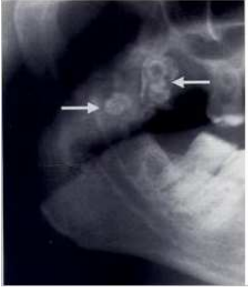

14.下圖為A、B、C三位病患之X光片,他們在接受右側上顎第一大臼齒之拔除時,發生牙根斷裂,此時若用拔牙挺挖取齒槽中斷 裂之牙根,那位病患之斷根被推擠入上顎竇之風險最高?

(A)A (B)B (C)C (D)三位病患之風險相同